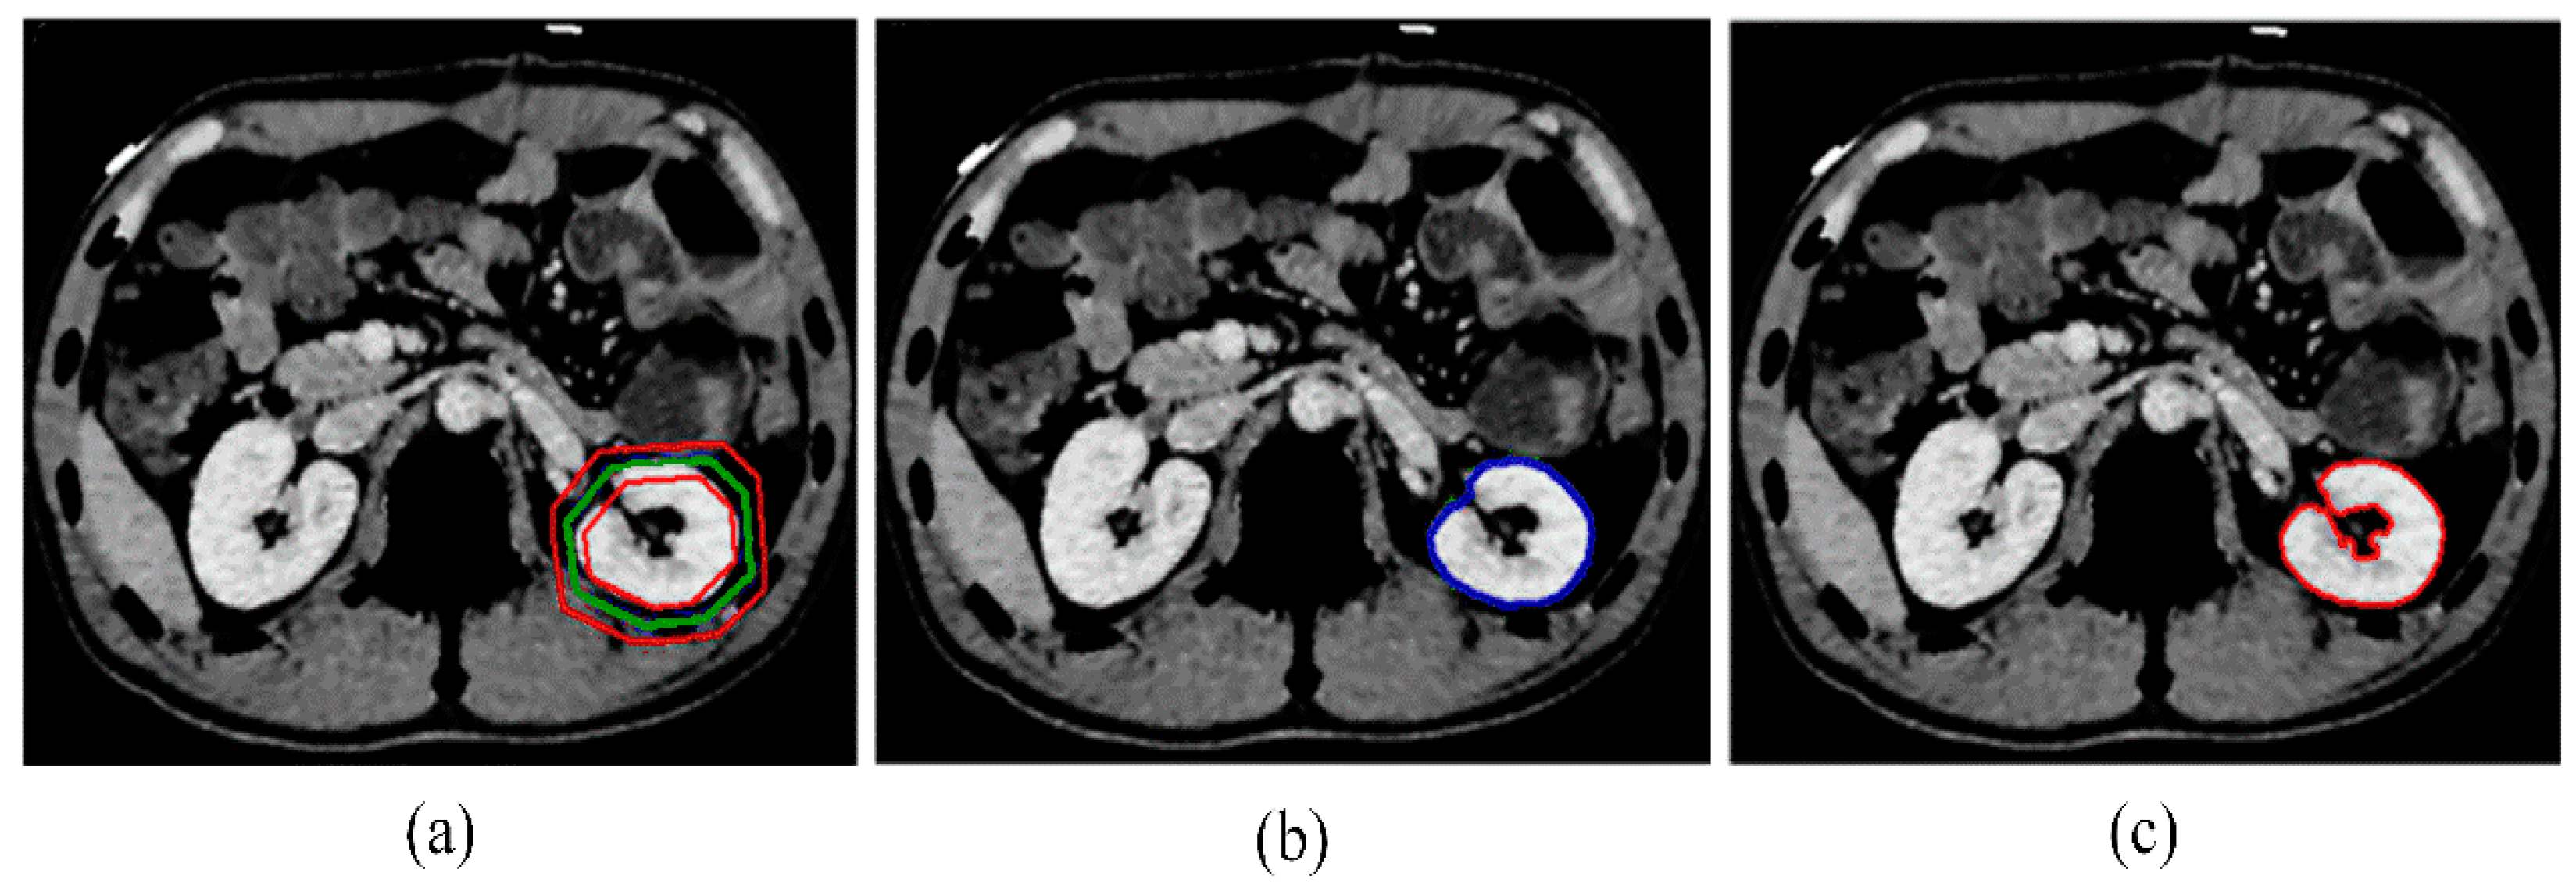

Accurate kidney segmentation in computed tomography (CT) scans is a crucial task for computer-aided systems that assist physicians and doctors in various tasks, including diagnosing renal diseases, locating pathological tissues, and planning radiotherapy [1]. However, effective kidney segmentation presents significant challenges due to several factors: (i) Poor image quality and intensity inhomogeneity within the kidney, where different regions, such as the cortex and medulla, have distinct gray levels, as illustrated in Figure 1a. (ii) Similarity in intensity between the kidneys and neighboring tissues, as shown in Figure 1b. (iii) Low intensity of kidney tissues, as depicted in Figure 1c. Additionally, variability in CT image reconstruction kernels can further complicate segmentation accuracy, affecting how kidney structures are delineated across different scans.

Figure 1. Typical kidney CT images displaying different challenges: (a) intensity inhomogeneity, (b) intensity similarity between kidneys and their adjacent tissues, and (c) low intensity of kidneys.